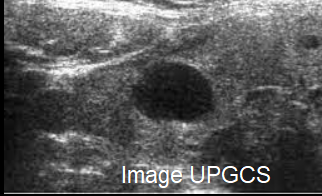

Quelle imagerie pour les pathologies de la thyroïde ? Recommandations de la HAS

Comment mieux prendre en charge les pathologies de la thyroïde ? Dans quelles situations une échographie est-elle pertinente ? Quand faut-il faire une cytoponction ? La HAS et le Conseil national professionnel de radiologie et d’imagerie médicale publient aujourd’hui une recommandation qui fait le point sur l’indication de ces examens. Les objectifs sont de réduire les échographies non pertinentes en cas de dysthyroïdies, d’améliorer le recours à l’échographie pour caractériser les nodules